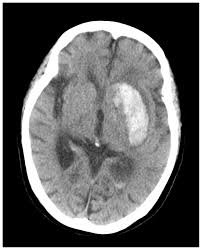

脳 室脳 穿脳 破脳 と脳 は脳 看護脳 97G102脳 |脳 脳出血脳 国試脳 |脳 テコプラ脳 脳卒中患者様のリスク管理に必要なこと脳 |医療脳 看護脳 介護のセミナー・研修情報サイト脳 メデュケーション脳 病気がみえる